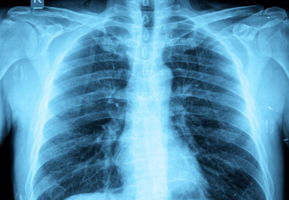

In COPD, the gaseous exchange is impaired due to the causes of COPD, inflammation in the lungs, damaged lung tissue and a narrowing of the airways which all makes breathing difficult.

Not inflating and not deflating the lungs fully can reduce the amount of oxygen absorbed and the amount of carbon dioxide expelled. To encourage better gaseous exchange especially in a COPD condition breathing exercises may help.